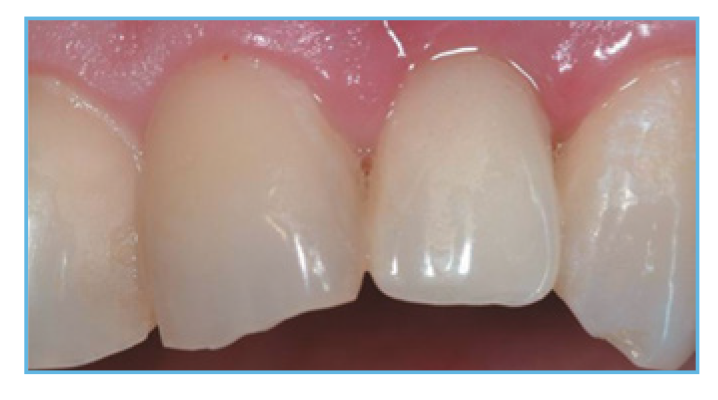

If you seek aesthetic implant level provisional restorations, PreFormance Provisional Components may be customized chairside or at the laboratory for specific contours and anatomic profiles.

Fig. 5. The provisional restoration was fabricated, occlusal and interproximal contacts were checked, adjusted accordingly, and delivered to the patient.